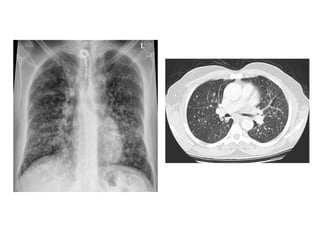

50-year-old man with long-standing history of heavy cigarette smoking,

dyspnea, cough, and smoking-related interstitial lung disease,

proven at biopsy, unenhanced axial CT image through mid to lower

lungs shows diffuse centrilobular ground-glass nodules bilaterally